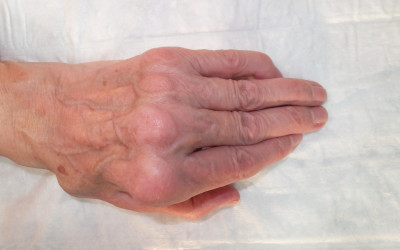

I have a bump on my wrist: the synovial cyst or ganglion

Created:18-12-2015 || Updated: 10-02-2020